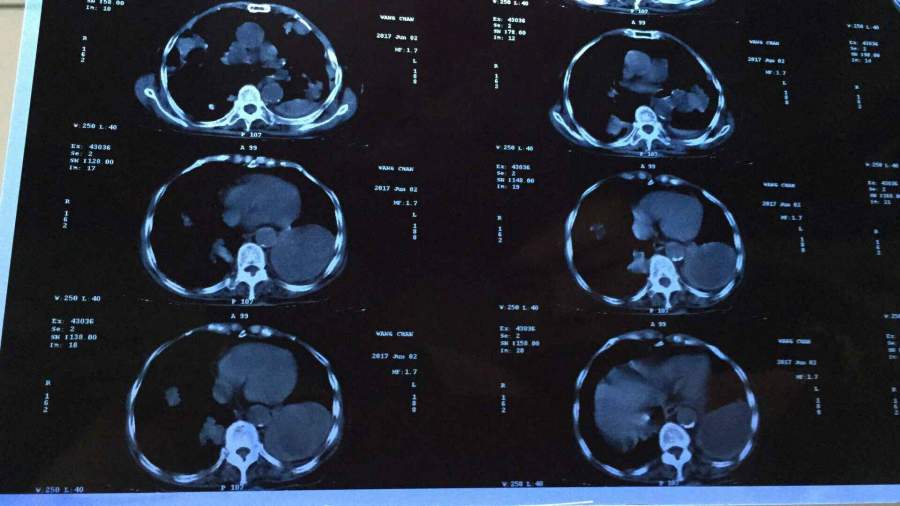

ÄÄλ´óÉñ£¬Äܹ»Ïêϸ½éÉÜϼ¸ÕÅctƬ×Ó ÒÑÓÐ3È˲ÎÓë

¼ÒÀïÍâÆÅµÄƬ×Ó£¬ÊǷΰ©£¬Ï£Íû¿ÉÒÔ´óÉñÏêϸ½éÉÜϲ¡±äÇé¿ö ·¢×ÔСľ³æAndroid¿Í»§¶Ë |

ÎÒ²»ÊÇÒ½Éú£¬Ö»ÄÜ˵·Î²¿µÄ°©±ä²¿·Ö»¹ÊÇ¿´×źÜÃ÷ÏԵ쬵ÚÒ»ÕÅÆ¬×ÓÖÐϱßÄǼ¸²ã£¬·Î²¿Öмä¸ßÁÁµÄ²¿·Ö¡£Ç°¼¸Ìì¸Õ¿´¹ý¼ÒÈËÀàËÆµÄƬ×Ó![]() ·¢×ÔСľ³æAndroid¿Í»§¶Ë |

Õâ¸öÖ»ÊÇÆÕͨCTƽɨ£¬¿´×ÅÏñ×ó·ÎÏÂÒ¶Ö×Áö£¬Ë«·Î¶à·¢×ªÒÆ£¬¸Î¼Ì·¢¶ñÐÔÖ×Áö´ý³ýÍâ¡£²»ÖªµÀÓÐûÓÐÈ¥Ò½Ôº¾ßÌåϵͳÖÎÁÆ ·¢×ÔСľ³æAndroid¿Í»§¶Ë |